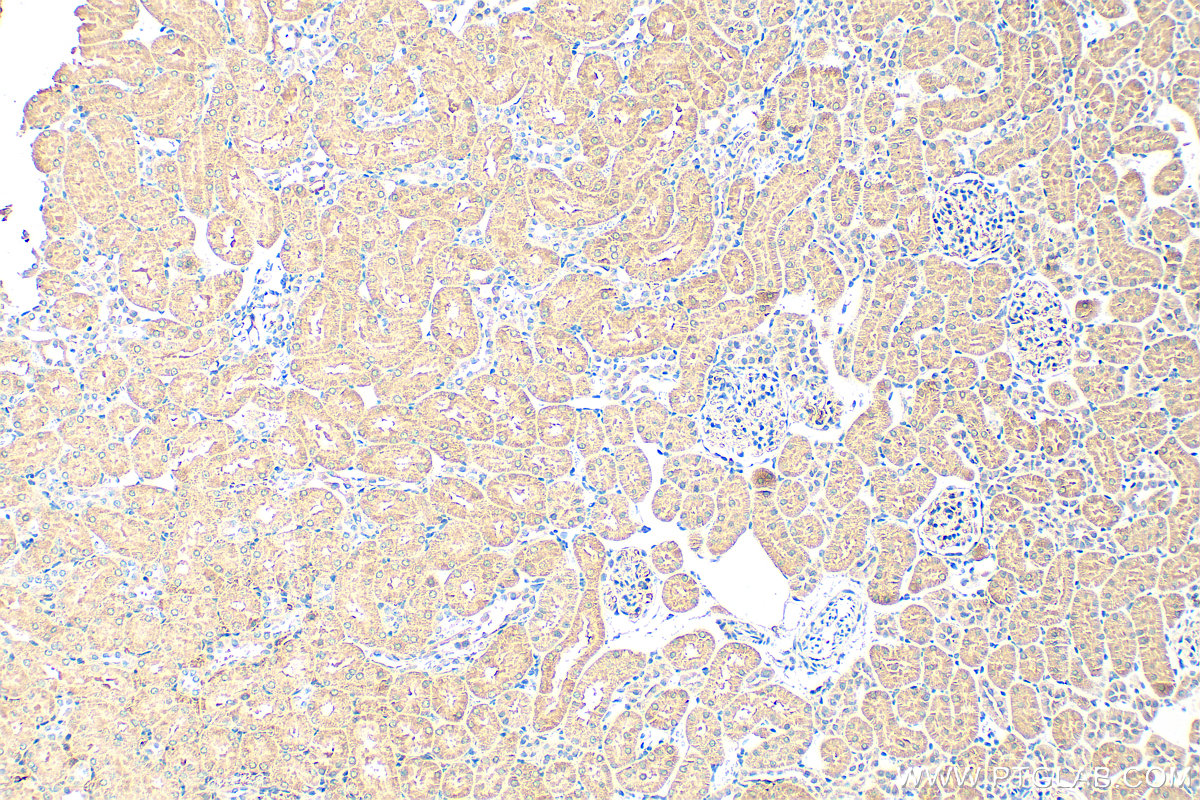

| Positive IHC detected in | rat kidney tissue, human thyroid cancer tissue, mouse kidney tissue, rat ovary tissue Note: suggested antigen retrieval with TE buffer pH 9.0; (*) Alternatively, antigen retrieval may be performed with citrate buffer pH 6.0 |

| Immunohistochemistry (IHC) | IHC : 1:500-1:2000 |